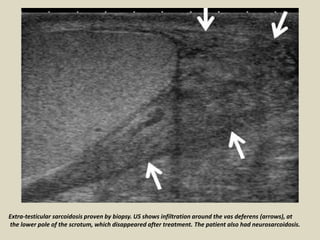

Extra-testicular sarcoidosis proven by biopsy. US shows infiltration around the vas deferens (arrows), at

the lower pole of the scrotum, which disappeared after treatment. The patient also had neurosarcoidosis.